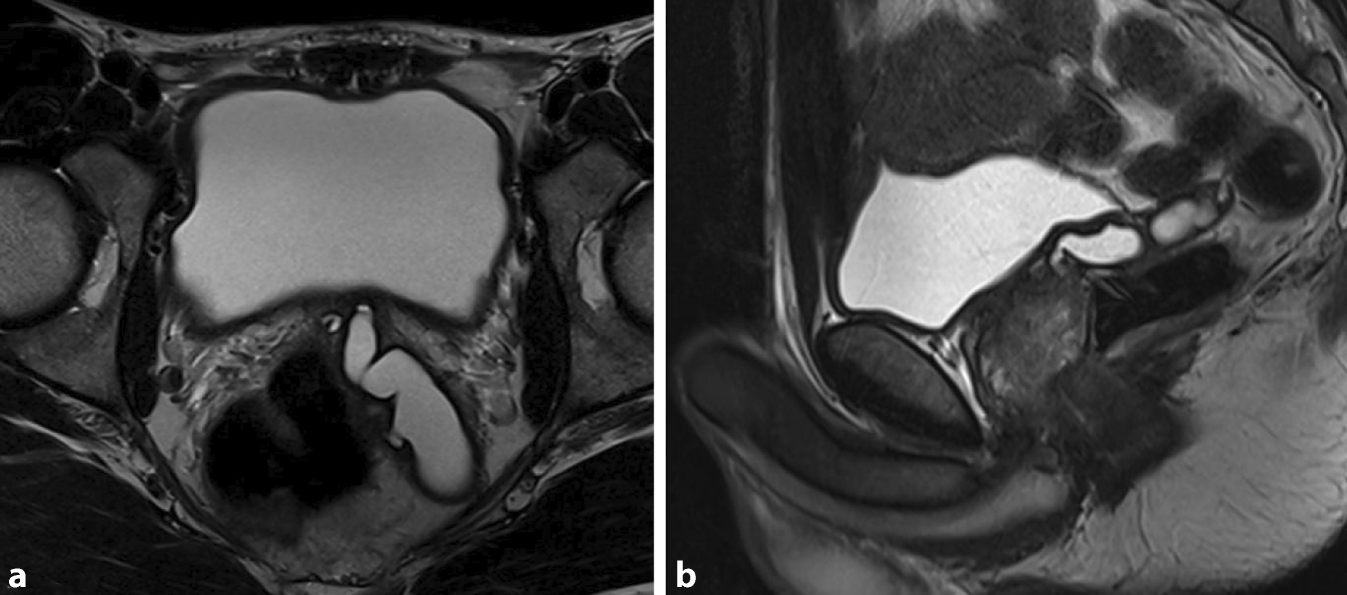

Sonographisch ließ sich eine prominente linke Samenblase im transvesikalen Ultraschall darstellen, sodass eine Bildgebung des Beckens mittels MRT durchgeführt wurde (Abb. 1 und 2). Hier zeigte sich ein zystisch dilatiertes Vas deferens sowie eine deutlich dilatierte Samenblase links bei nicht darstellbarem Vas deferens und Samenblasenagenesie rechts. Zum Ausschluss eines Zinner-Syndroms erfolgte neben einer Sonographie des oberen Harntrakts auch die weitere Diagnostik mittels MRT Abdomen. Bei regelrechtem Befund beider Nieren konnte ein Zinner-Syndrom ausgeschlossen werden.

Abb. 1

Sonographiebefund von transvesikal mit prominenter linker Samenblase dorsal der Harnblase